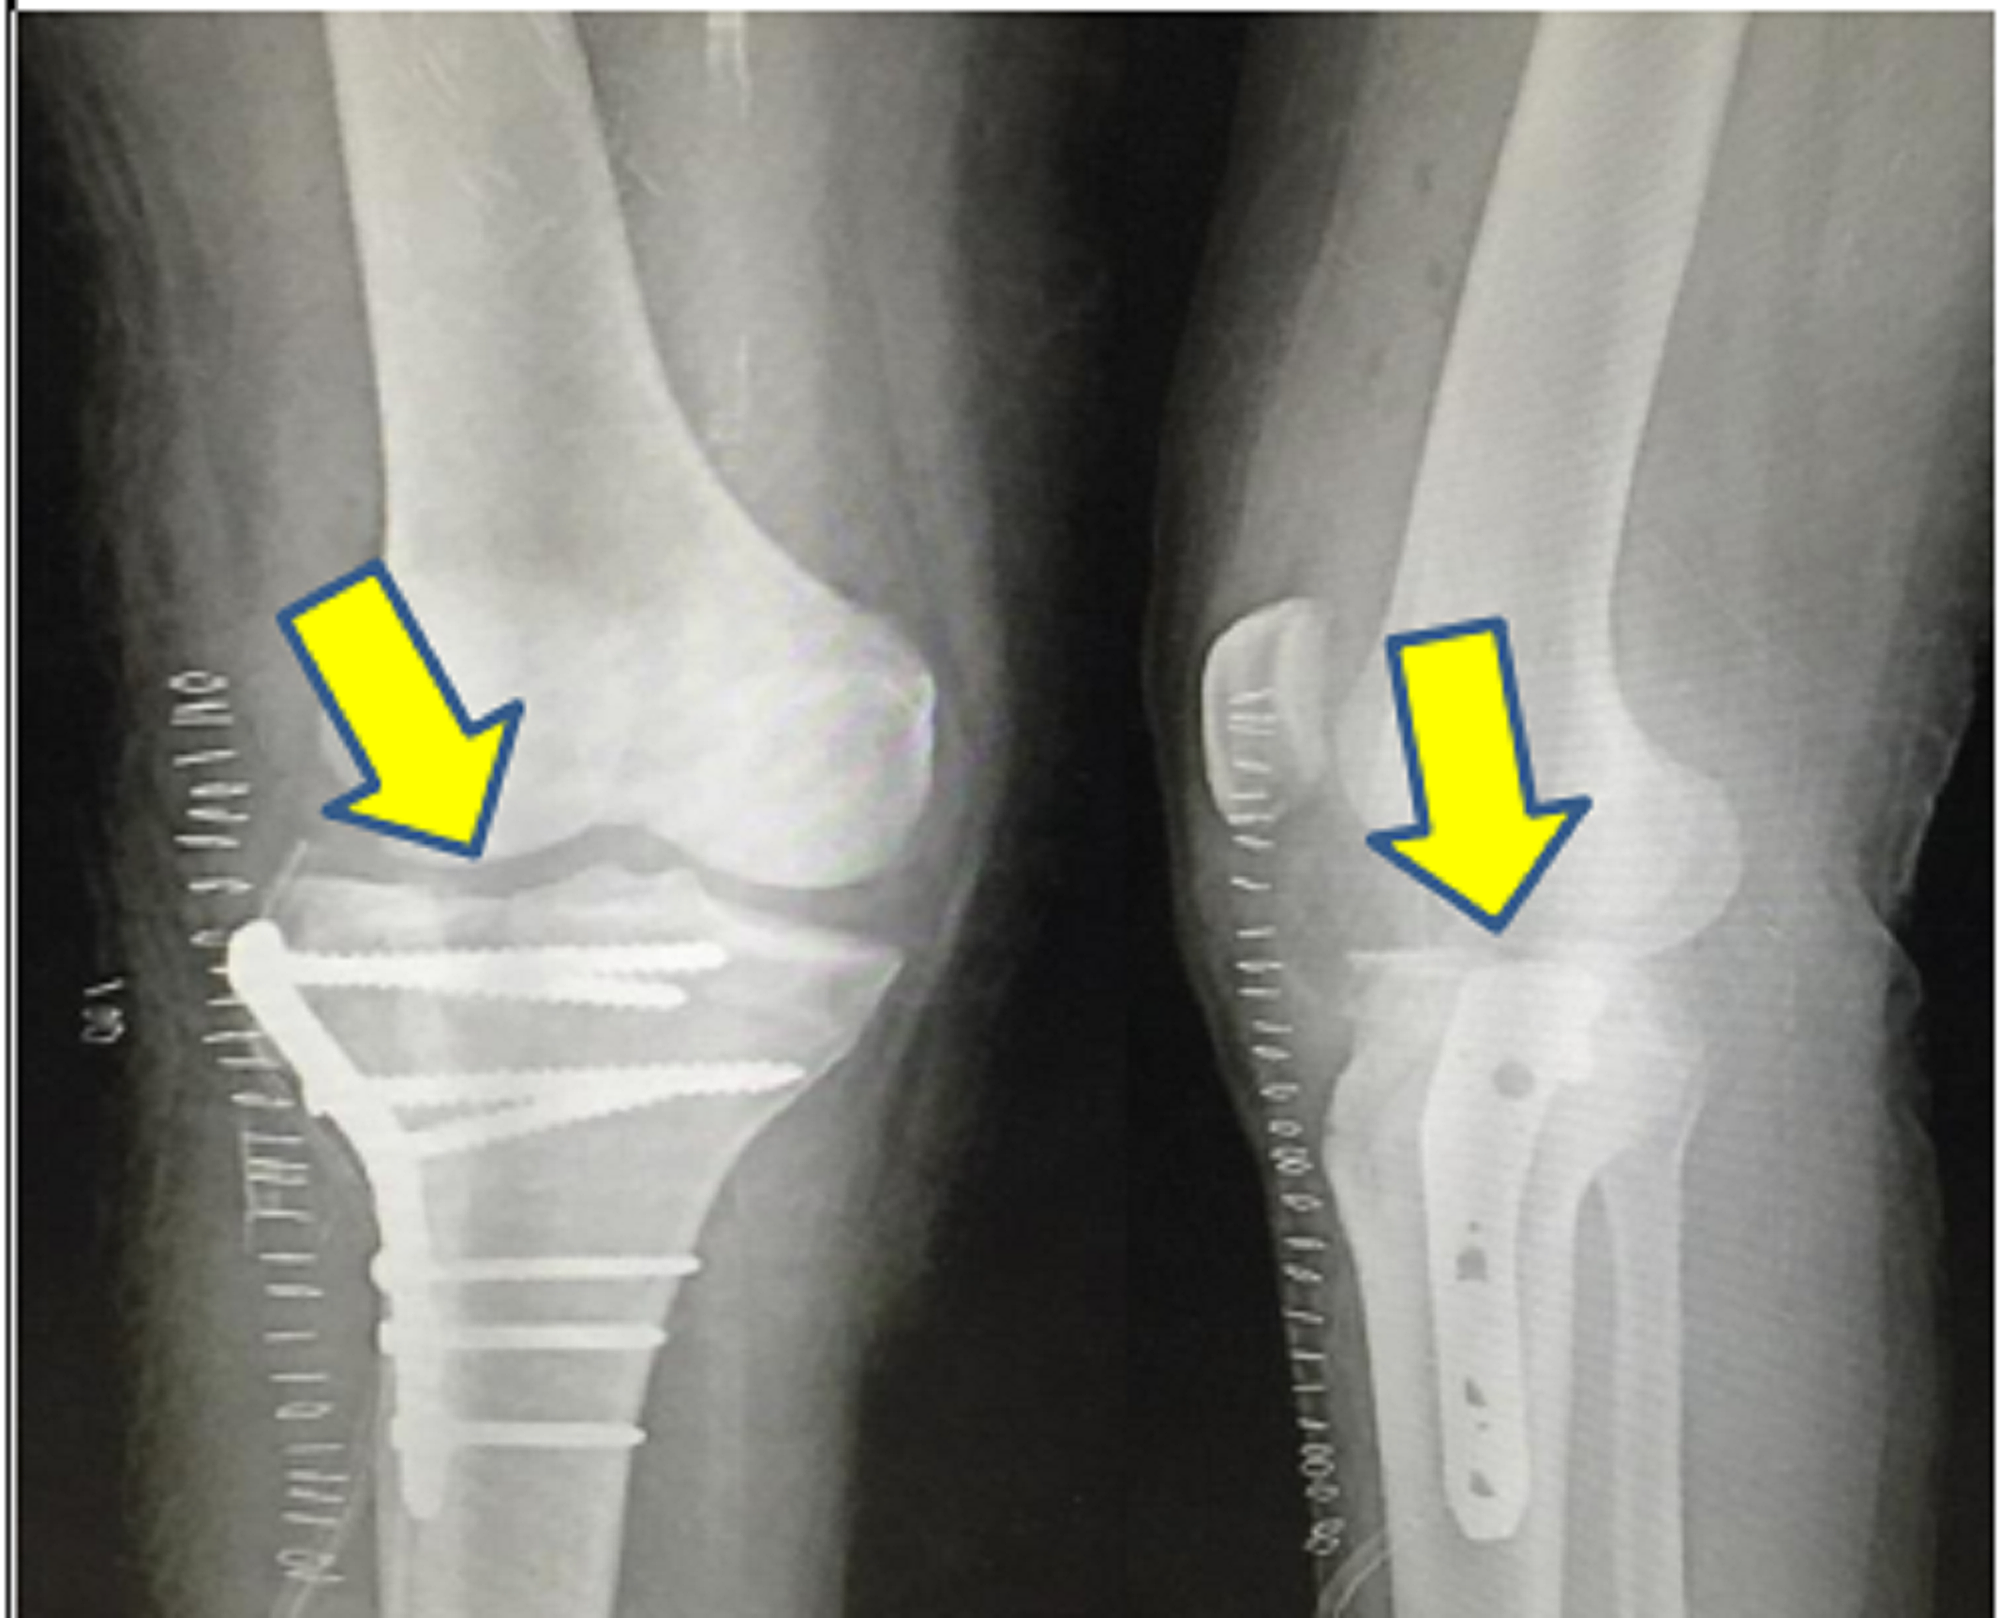

The patient was initially managed with intravenous administration of amoxicillin- potassium clavulanate 1.2 g prophylactically. The patient was then temporarily stabilized with an above-knee fiberglass splint. He was sent for preoperative imaging, as shown in Figure 1. Plain radiograph of the right knee showed split fracture involving the lateral tibial condyle extending into the articular surface, with lateral displacement of fracture fragments, and oblique fracture of fibular head with caudal displacement of fracture fragments. MRI of the right knee showed a high-grade tear in the proximal aspect of the lateral collateral ligament and a grade 2 medial collateral ligament tear. In addition, the patient was counselled regarding expectations and outcomes. After obtaining informed consent, the patient was operated under spinal anesthesia. Open reduction and internal fixation with proximal tibia locking compression plating with autologous bone grafting from the ipsilateral iliac crest (corticocancellous graft) along with lateral meniscectomy and arthrolysis of the knee joint was performed under spinal anesthesia, as shown in Figure 2. The post-operative period was uneventful.

Post-operatively, the patient received intravenous amoxicillin-potassium clavulanate 1.2 g twice daily for seven days and amikacin sulfate 500 mg twice daily for five days followed by oral amoxicillin-potassium clavulanate 625 mg twice daily for seven days. Post-operative radiograph of the operated knee joint was taken on post-operative day 2, as shown in Figure 3. An above-knee slab support was applied, and the patient was advised strict non-weight bearing for six weeks. Culture and sensitivity from surgical site showed staphylococcus epidermidis, which was sensitive to tetracycline and doxycycline. The patient was started on tablet doxycycline 100 mg twice a day for 14 days. All staples were removed on post-operative day 14, and the surgical site was found to be healthy. The patient underwent physiotherapy in the form of muscle stimulation test 15 minutes daily till he recovered from the foot drop. The guarded continuous passive motion was also started for the patient. At discharge, range of motion at the knee joint was 0- to 120-degree flexion after one month of physiotherapy. Tinel sign was positive 1-cm along the common peroneal nerve distribution at the level of the middle third of the leg. The patient had recovered from the foot drop (possibly due to neuropraxia). Partial weight bearing was initiated after six weeks. The patient was allowed full weight bearing at three months. At the last follow-up, six months post-injury, he was walking without any difficulty.